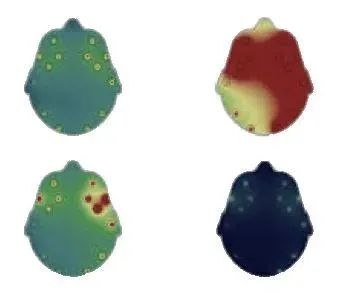

对于白色背景,我们首先创建一个白色画布,然后通过使用OpenCV函数“ drawContours()”绘制轮廓为黑色(R,G,B = 0,0,0)且厚度为FILLED的轮廓,如下所示创建颜色反转的蒙版(-1)。

用于ROI提取的备用倒置掩模(图像源作者)

然后,我们使用OpenCV “ add()”函数将此反向蒙版添加到先前获得的黑色背景中,并获得相同的结果,但使用白色背景。

在白色背景上提取的ROI